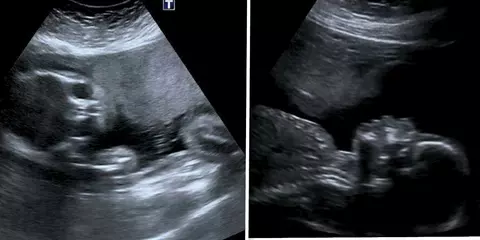

Stacey Astley (38 de ani), din Tauton, Someset, Marea Britanie, susține că a văzut chipul unui înger în ecografia de 20 de săptămâni a bebelușului pe care-l aștepta. Femeia mai are patru copii și a pierdut trei sarcini în încercarea de a-l face pe cel cu numărul cinci. Stacey spune că îngerul păzitor din ecografie a ajutat-o să aducă pe lume copilul pe care și-l dorea și pe care îl credea imposibil de făcut după pierderile de sarcină.

„La scanarea mea de 16 săptămâni, hematomul a scăzut în cele din urmă, iar la scanarea mea de 18 săptămâni a scăzut la jumătate din dimensiunea inițială. Sângerarea s-a oprit la 19 săptămâni, iar această fotografie cu îngerul păzitor a fost făcută la 20 de săptămâni.